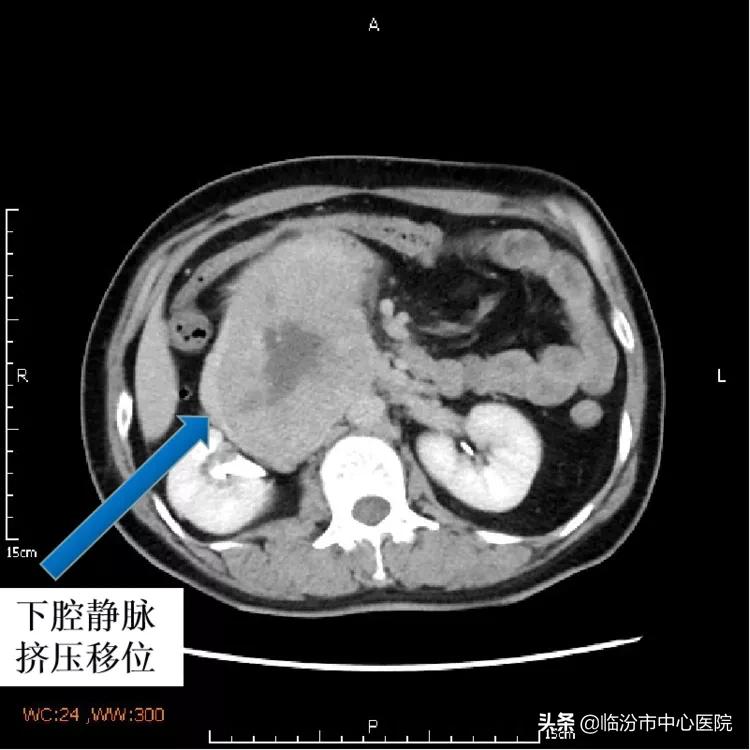

何女士来到市中心医院就诊后,行全腹盆CT检查发现肿瘤位于腹膜后方,体积较大,与腹主动脉、下腔静脉、右肾动脉等大血管关系密切,并且肿瘤的血供非常丰富,下腔静脉已经被巨大瘤体包裹移位,非常危险。

经过手术探查发现,肿瘤位于腹膜后,在腹主动脉与下腔静脉之间,与腹主动脉粘连,牵一发而动全身。下腔静脉被肿瘤包裹挤压,变形移位,在手术剥离中稍有不慎就会引起出血或坏死。